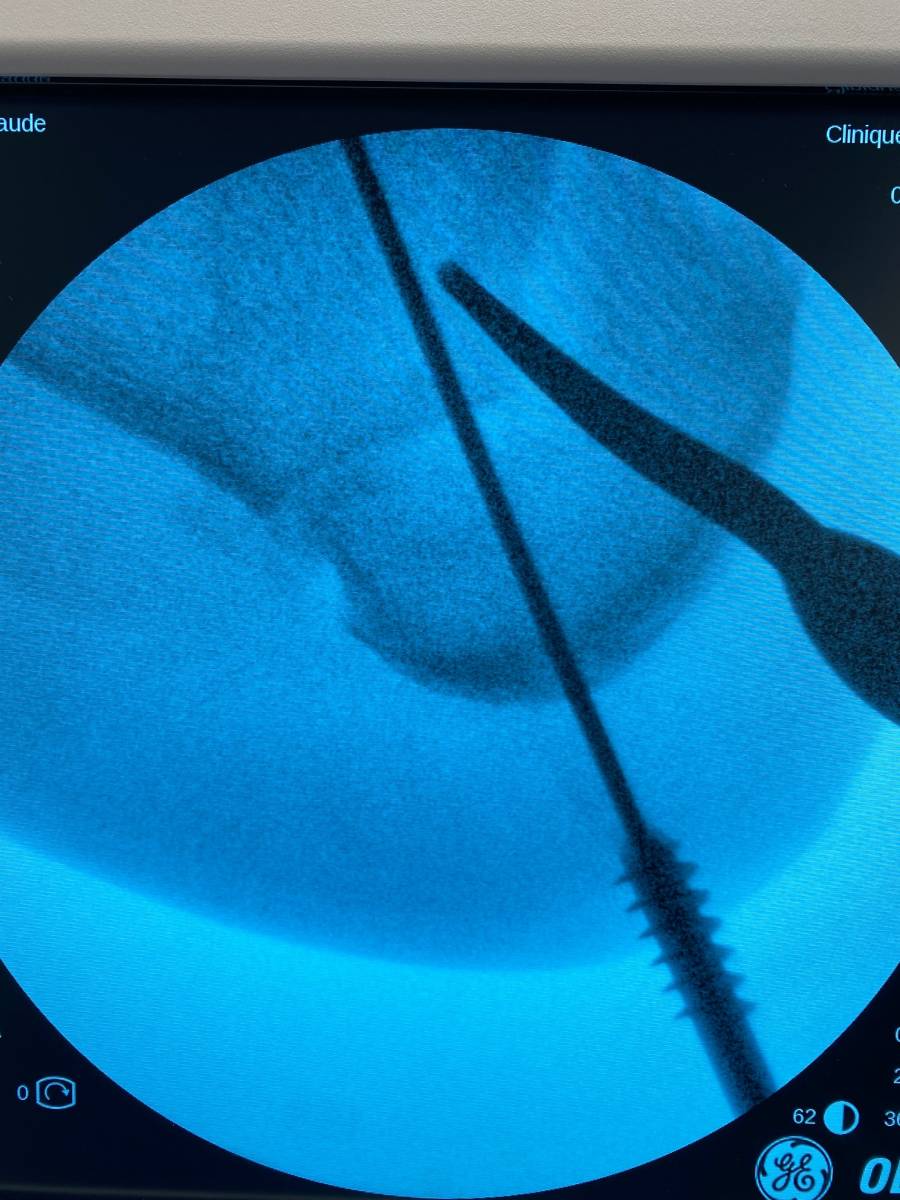

ostéotomie  calcaneum ICP PARIS

Une ostéotomie calcanéenne de valgisation sur arthrose varisante, qu'est-ce que c'est ?

Institut de la Cheville et du Pied, bloc opératoire de l'ICP Paris (Clinique Blomet)